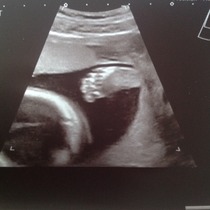

Well, had the scan yesterday and got some very cute photos, which I am attaching - one of his little foot, which is apparently 3cm long already! And he is definitely a boy!

His measurements are all spot on, and mostly his organs look good, but they were a bit concerned about his bowel which looked 'a bit bright' around the edges on the screen, so I am being referred to a consultant at the FMU.

They asked if I'd had any bleeding, as apparently the baby can ingest blood in the amniotic fluid which can make the bowel look bright, but I've not had any bleeding all pregnancy as far as I know (tho DH did point out that all my knickers are black - but I have checked every time I've wiped since October.) They said it was borderline whether or not it was actually a problem, but they would rather be over-cautious. However, they said lots of the doctors are on holiday next week because of half term, so god knows how long I will have to wait to be seen.

Bluebel those are lovely pics. Please don't talk to Dr Google. He always has the worst prognosis. Go with the professional assurances that all is ok.

They are beautiful photos!! I agree, never look up on google because it'll say so many different problems and you'll worry yourself silly! Im sure baby is okay Smile